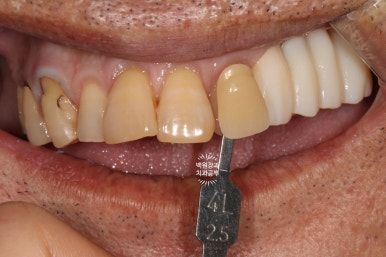

최대한 자연스러운 색상으로 제작해드리기 위하여, 남아있는 자연치인 위턱 앞니들과 유사한 색으로 임플란트 크라운을 제작해드리기로 하였습니다.

저희가 가지고 있는 VITA Shadeguide 기준으로 4L 2.5의 색상으로 측정되었네요.

다소 어둡고 yellowish한 느낌의 치아색상입니다.